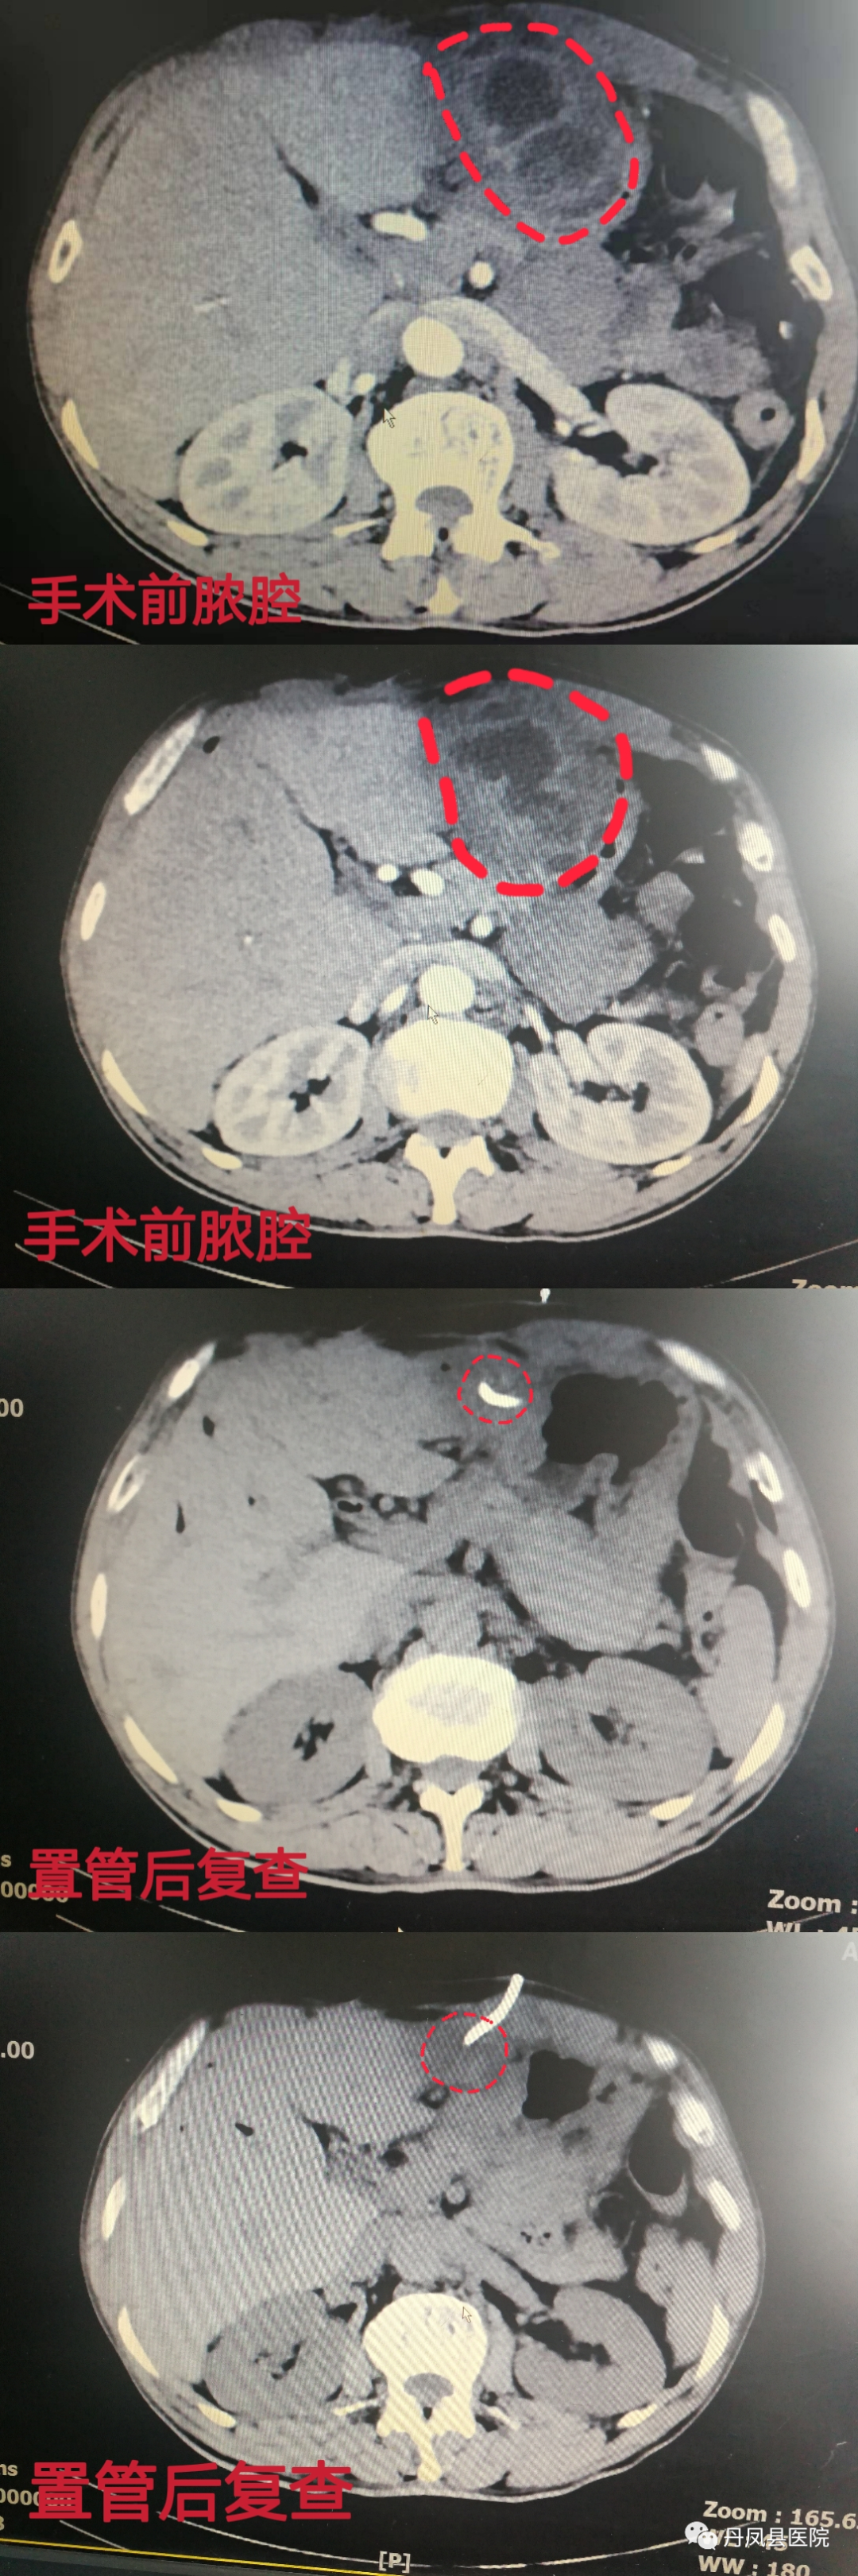

外一科为一例肝脓肿患者成功实施手术

患者李某,男,57岁,于2022年1月9日在外一科门诊就诊。主诉:胆肠吻合术后10年,上腹剧烈疼痛5天余。院长樊书满在门诊查看病人后收入外一科住院治疗。入院后外一科主任王超为病人做详细查体,并立即安排相关检查,经过王超主任和田金朝副主任医师与影像科、超声科医生紧密合作,诊断为肝脓肿,并为患者制定合理的手术方案:超声引导下肝脓肿穿刺置管引流术。1月12日,行肝脓肿穿刺引流术,手术过程顺利。术后患者腹痛、腹胀症状完全消失,体温逐渐恢复正常,复查CT及彩超可见脓液已完全引流。